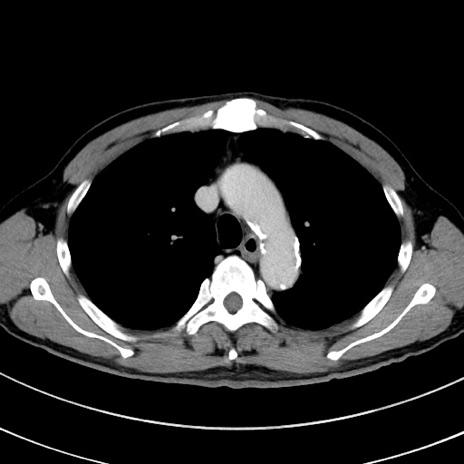

冠状断像

【症例】 60歳代男性

【主訴】 黒色吐物

【現病歴】 4日前から嘔気自覚、2日前の朝食後にも嘔気あり、自分で手で嘔吐反射起こし嘔吐したところ血が混ざっていたため受診。

【既往歴】 5年前汎発性腹膜炎を伴う急性虫垂炎で手術、高血圧、前立腺肥大症、高脂血症

【身体所見】 腹部正中に手術癩痕あり 腹部平坦・軟圧痛なし膨満感あり

【データ】WBC 8400、CRP 4.54